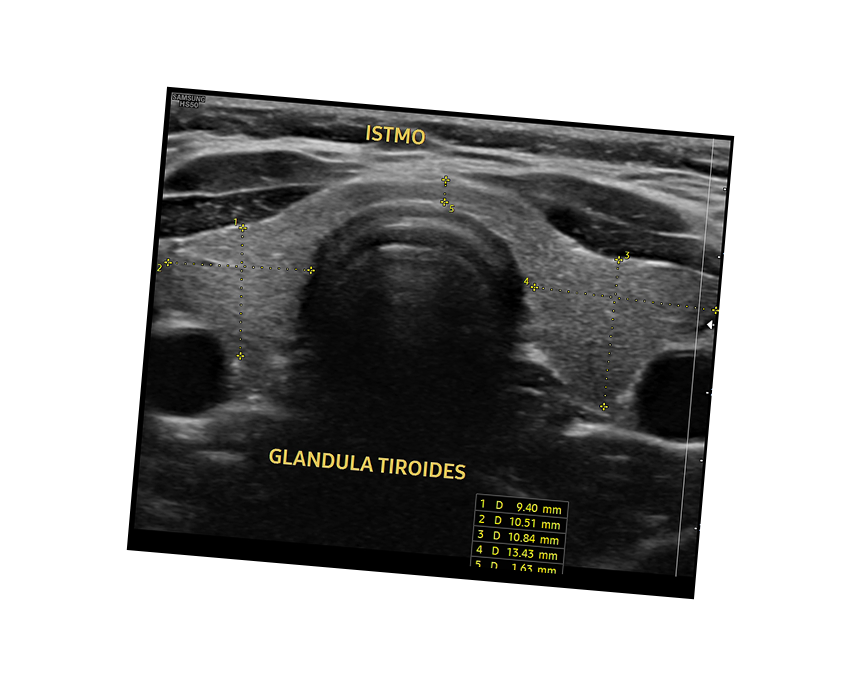

Ecografía de Tiroides

- nódulos tiroideos

- bocio(agrandamiento de la tiroides)

- evaluación de masas cervicales

- disfunción tiroidea: híper e hipotiroidismo

- cáncer de tiroides